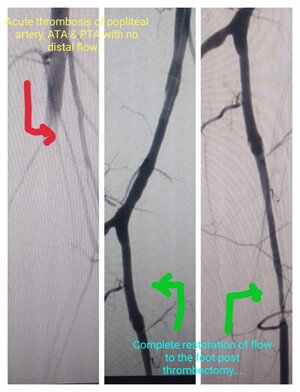

Thrombectomy - Pre & Post